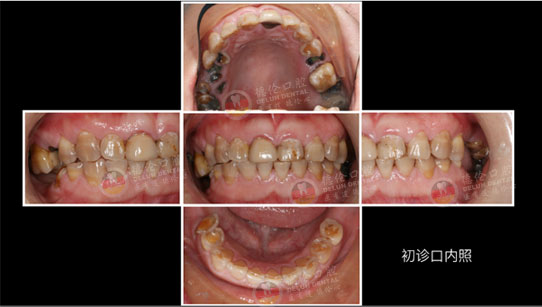

李医生诊疗案例